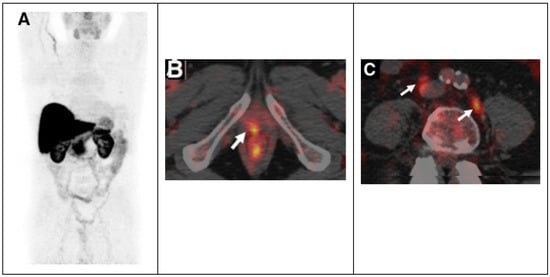

Subsequently, Piccardo A. et al. prospectively evaluated the biodistribution, dosimetry and lesion kinetics in 50 PCa patients with biochemical relapse after surgery or radiation therapy []. This study compared the diagnostic performance of 64Cu-PET/CT, 18F-choline PET/CT, and multiparametric MRI (mpMRI). The results showed the effectiveness of 64Cu-PET/CT in detecting local relapse along with bone and nodes metastases (Figure 2).

Figure 2.

64CuCl2 PET/CT in prostate cancer relapse. (A) 64CuCl2 biodistribution with high activity in the liver, and kidneys and lesser in the bowel. 64CuCl2 PET/CT image of pelvis from a old man treated with radical prostatectomy with rising PSA level demonstrated copper-avid recurrence in vescicourethral anastomosis (B) and nodes (C). Adapted from ref. [] with (This research was originally published in JNM. A. Piccardo et al. 64CuCl2 PET/CT in prostate cancer relapse. J. Nucl. Med. 2018, 59, 444–451. ©SNMMI).

The detection rate (DR) of 64Cu-PET/CT was higher than the DR of 18F-choline PET/CT and multiparametric MRI, particularly in patients with biochemical relapse and a low PSA level []. The success of 64Cu-PET/CT can be related to the better biodistribution than 18F-choline PET/CT; copper ions are not eliminated via the kidneys and do not concentrate in the urinary tract, and this allows an accurate evaluation of the pelvic region and prostatic bed with early visualization of pelvic lesions. Furthermore, dosimetry studies showed that the dose absorbed by PCa recurrences and metastases is low, not considering the therapeutic effect of Auger electrons []. More recently, it has been demonstrated that 64Cu-PET/MRI shows a higher overall DR in the evaluation of PCa local recurrence than the DR of 18F-Choline PET/MRI, 64Cu-PET/CT, 18F-Choline PET/CT and mpMRI alone [].